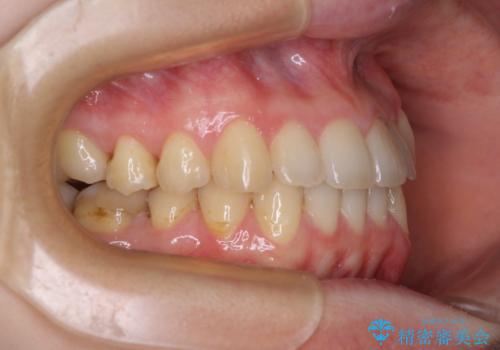

- 八重歯を気にして来院された患者様です。

診査を行ったところ、下顎前歯が1本欠損しており、下顎歯列が上顎よりも小さくなっていることで、上顎にデコボコが生じていました。

口元を見ると抜歯をして突出感を改善するような状態ではなかったため、上顎歯列のデコボコを整えて、歯列全体を後方に移動させることでバランスを取ることとしました。